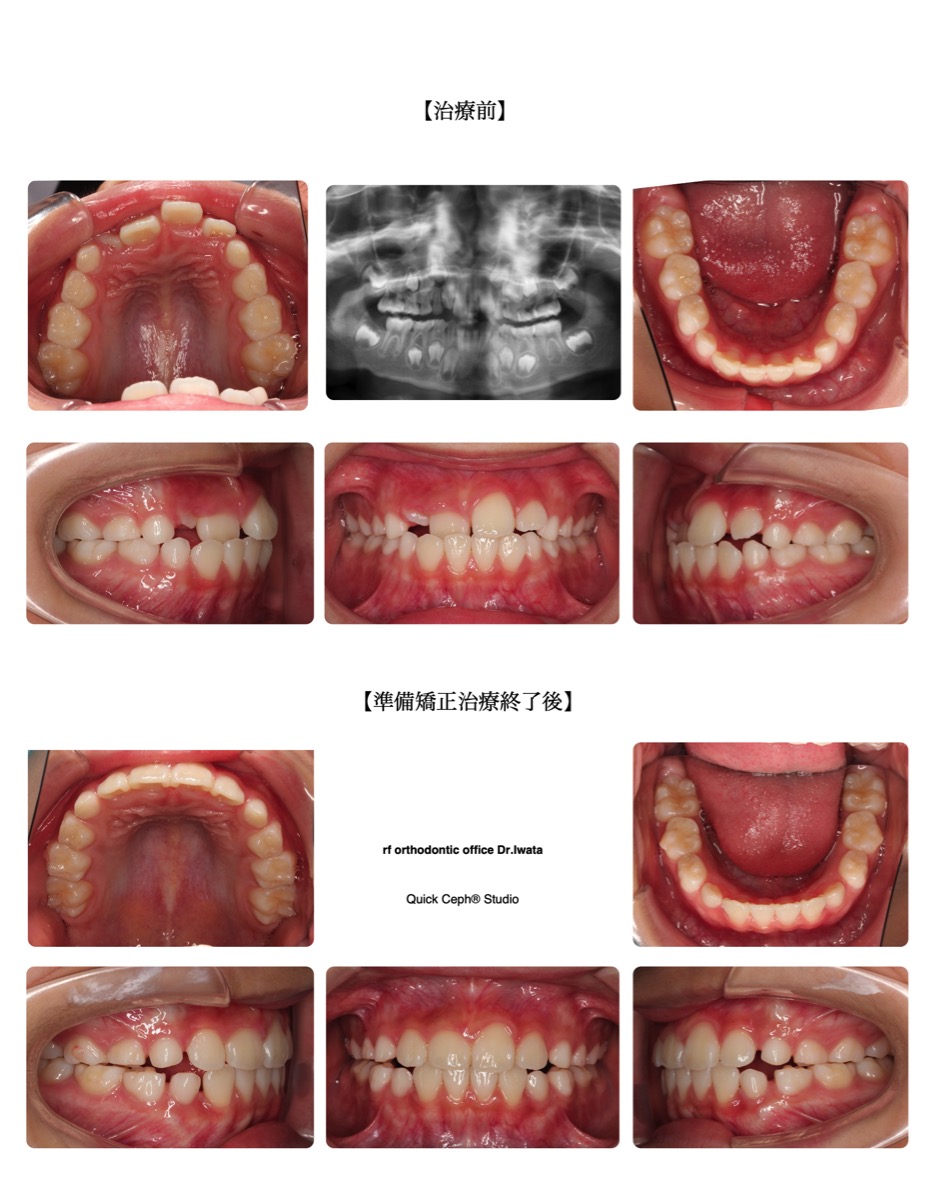

【主訴】上の前歯がガタガタしていて反対咬合になっている。

【主な症状】反対咬合 叢生

| 治療方法 | マウスピース型矯正装置 |

| 治療期間・回数 | 12ヶ月・11回 |

| 性別 | 男性 |

| 年齢 | 7歳 |